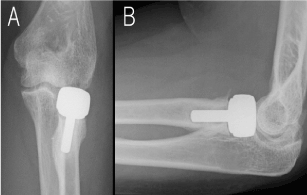

A previously healthy woman in her 50s fell while riding her bicycle and injured her left radial head fracture (AO21-B2.3, Mason Type 3; Figures 1A and 1B). Although osteosynthesis was attempted with an LCP Radial Head Rim Plate, intraoperative findings indicated severe radial head comminution, resulting in poor plate fixation (Figure 1C). Therefore, the radial head was removed, a radial head made with bone cement was used to fix the diaphysis with the plate, and surgery was concluded. Postoperatively, left elbow range of motion (ROM) was -30/110° and external/internal rotation (ER/IR) was 25/60°. Two months after initial surgery, radial head replacement was performed using an EVOLVE implant (Figures 2A and 2B). At 6 months postoperatively, the left elbow improved to ROM -20/130°, with ER/IR 90/90°. Motion was smooth and daily lifestyle was not impaired, although the patient experienced pain in her elbow when lifting heavy objects.

Figure 2.A The anteroposterior radiograph shows radial head replacement B. The lateral radiograph shows radial head replacement.